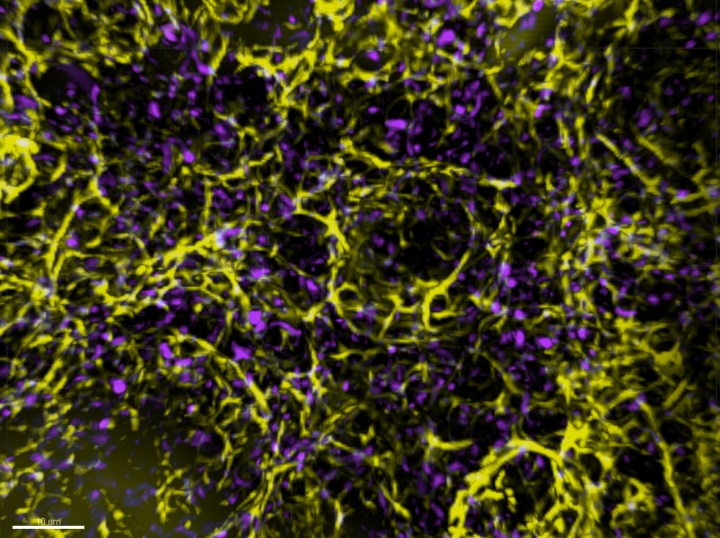

Published in Science Advances, the study performed high-resolution imaging and revealed that the neighbouring cells have a process that applies mechanical force to split the dying cells into smaller fragments before consuming them.

Photo caption: Optically cleared tissue sections of the thymus. Yellow - epithelial cells; Magenta - dying cells.